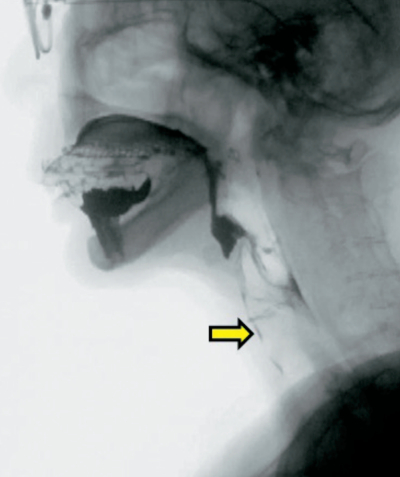

79歳の男性。食事時のむせを主訴として来院した。嚥下造影検査の画像を別に示す。

矢印で示す所見はどれか。1つ選べ。

a. 誤嚥

b. 鼻腔逆流

c. 喉頭侵入

d. 梨状窩残留

e. 喉頭蓋谷残留